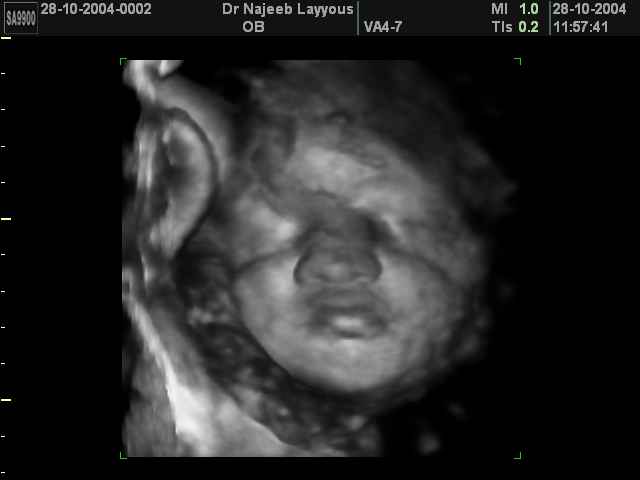

صور لوجه الجنين بجهاز الالتراساوند ثلاثي الأبعاد | الدكتور نجيب ليوس

صور لوجه الجنين بجهاز الموجات فوق صوتية ثلاثي الأبعاد